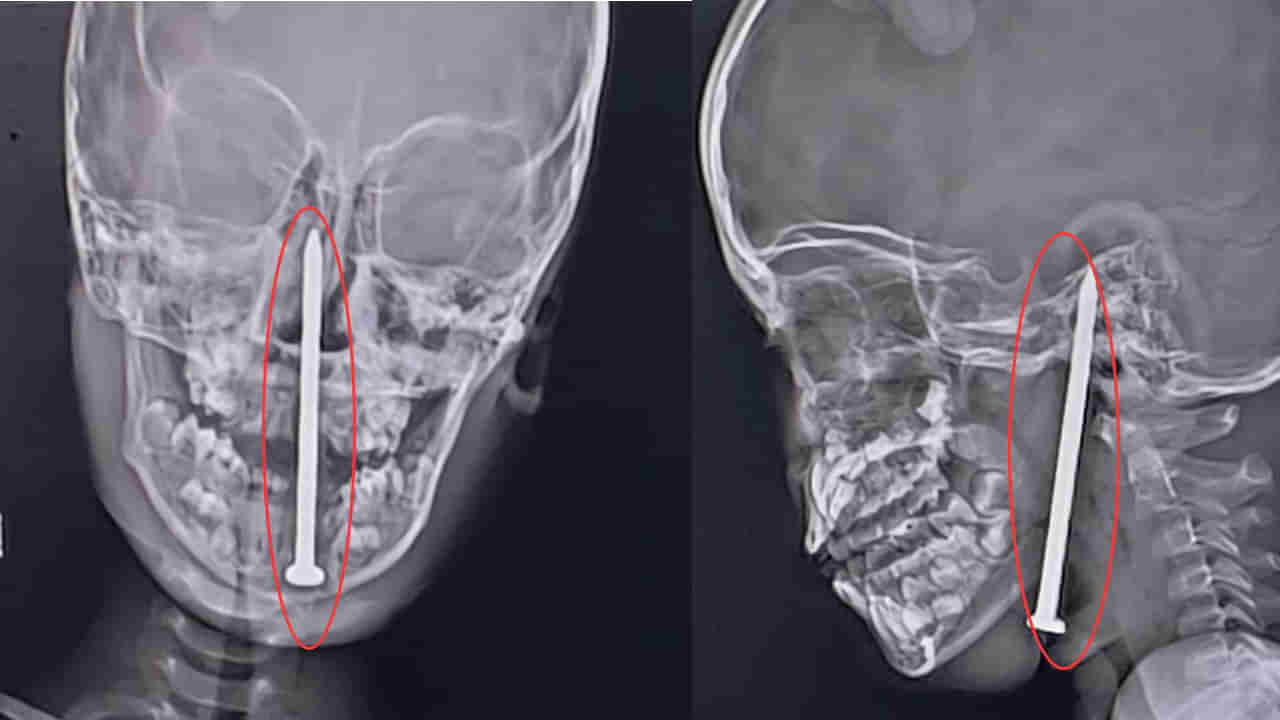

లక్నోలోని కింగ్ జార్జ్ మెడికల్ యూనివర్సిటీ (KGMU) వైద్యులు అరుదైన శస్త్రచికిత్సను విజయవంతంగా చేసి, 7 ఏళ్ల బాలుడి మెదడులోకి మెడ ద్వారా వెళ్లిన 8 సెంటీమీటర్ల ఇనుప మేకును తొలగించారు. ఈ శస్త్రచికిత్స దాదాపు 10 గంటలపాటు సాగింది.

బాలుడు ఉత్తరప్రదేశ్లోని బలరాంపుర్ జిల్లాలోని నవాజ్పుర్ గ్రామానికి చెందినవాడు. మే 15న ఆడుకుంటున్నప్పుడు కిందపడిపోయి, మెడలోకి మేకు దూసుకెళ్లింది. అది మెదడుకు వెళ్లి అక్కడే కూరుకుపోయింది. కుటుంబ సభ్యులు మొదట అతడిని ప్రైవేట్ ఆసుపత్రికి, ఆపై బలరాంపుర్ జిల్లా ఆసుపత్రికి తీసుకెళ్లారు. అక్కడి నుండి అతడిని లక్నోలోని KGMU ట్రామా సెంటర్కు తరలించారు.

అక్కడ డాక్టర్ సమర్, డాక్టర్ అశుతోష్ మే 16న తెల్లవారుజామున 1 గంటకు బాలుడిని పరిశీలించారు. మేకు మెదడులోకి వెళ్లి, రక్తనాళాలను డ్యామేజ్ చేయలేదని గుర్తించారు. ఈ కేసు చాలా క్లిష్టమైనదని, బాలుడి ప్రాణాలే ప్రమాదంలో ఉన్నాయని వారికి అర్థమైంది. న్యూరోసర్జరీ, ENT నిపుణులతో కలిసి సమావేశమై శస్త్రచికిత్స చేయాలని నిర్ణయించారు. ఆ రాత్రే 10 గంటల సమయంలో సర్జరీ మొదలుపెట్టారు. ఈ చికిత్సలో డాక్టర్ వైభవ్ జైస్వాల్, డాక్టర్ సమీర్ మిశ్రా, డాక్టర్ యాదువేంద్ర, డాక్టర్ లోకేశ్, డాక్టర్ ఏక్తా తదితరులు పాల్గొన్నారు.

ప్రస్తుతం బాలుడు ఆరోగ్యంగా ఉండి వైద్య పర్యవేక్షణలో ఉన్నాడు. ఈ శస్త్రచికిత్స విజయవంతమవడం వైద్య రంగంలో ఒక చారిత్రాత్మక ఘట్టంగా నిలుస్తుందని, ప్రభుత్వ వైద్య సేవలపై ప్రజల్లో నమ్మకాన్ని పెంచుతుందని వైద్యులు తెలిపారు.